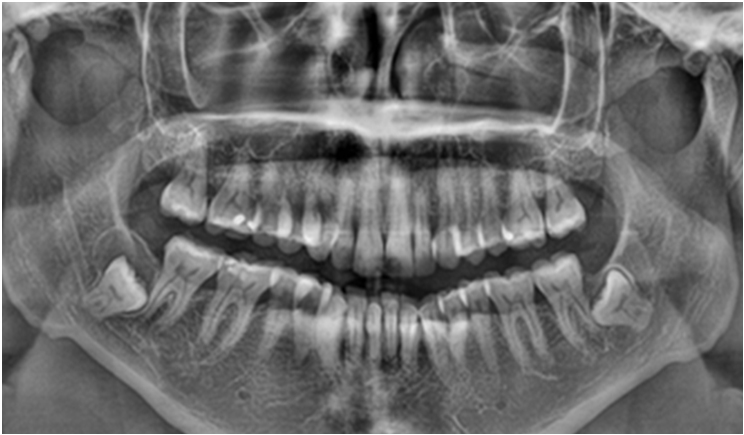

On an X-ray, the dentigerous cyst appears as a well-defined radiolucent area around the crown of the impacted tooth. It’s important to note that dentigerous cysts often don’t cause any symptoms and are found incidentally. However, if they grow in size or become infected, they can lead to swelling, pain, or displacement of nearby teeth.